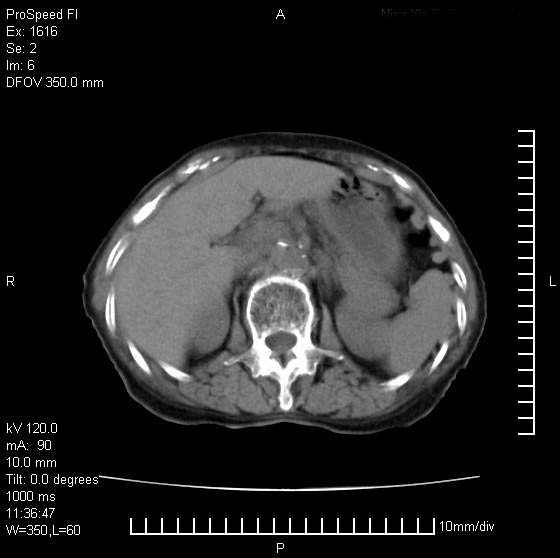

患者无明显临床症状,肝左叶发现一个圆形密度不均的低密度灶,边界较清楚,大小37x45mm,ct值35-70,患者犹豫做增强,如有增强片,我再发上,现先请各位老师会诊.

左肝外叶可见较大圆形低密度影,病灶可见较光整清晰边界,病灶内可见多量条状稍高密度影,右肝前叶亦可见圆形结节状低密度影,边界清晰,密度均匀,考虑1肝多发囊肿,左肝囊肿内出血2肝包虫病3左巨块型肝癌出血合并右肝转移或合并右肝囊肿

病灶内高密度影,从ct值上看是血的密度还是某种纤维组织呢?似乎有内缘有包膜,肝脏各叶比例略失调,脾脏有点大.

hcc(巨块型)伴出血,突破肝包膜,肝胃韧带内,腹主动脉旁淋巴结转移;肝硬化

肝左叶不均匀占位,内有斑片状高密度出血灶,内侧缘似有假包膜,腹主动脉周围及肝门区结构紊乱,似有增大淋巴结,考虑:肝左叶hcc并淋巴结转移。建议增强扫描除外其他。